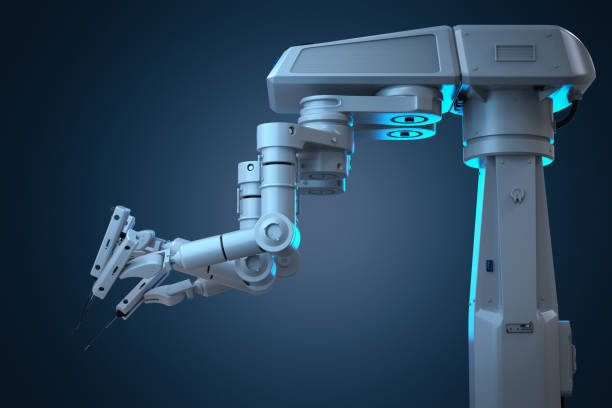

5. Robotic-Assisted Hip Replacement

It is an advanced surgical technique where a robotic arm assists the surgeon in planning and executing the procedure with extreme precision. Popular technologies like MAKO (Stryker), ROSA (Zimmer), and NAVIO guide real-time adjustments to preserve bone and achieve optimal implant positioning. This results in better long-term outcomes and faster functional recovery. It is especially ideal for younger, active patients or those requiring complex anatomical corrections.